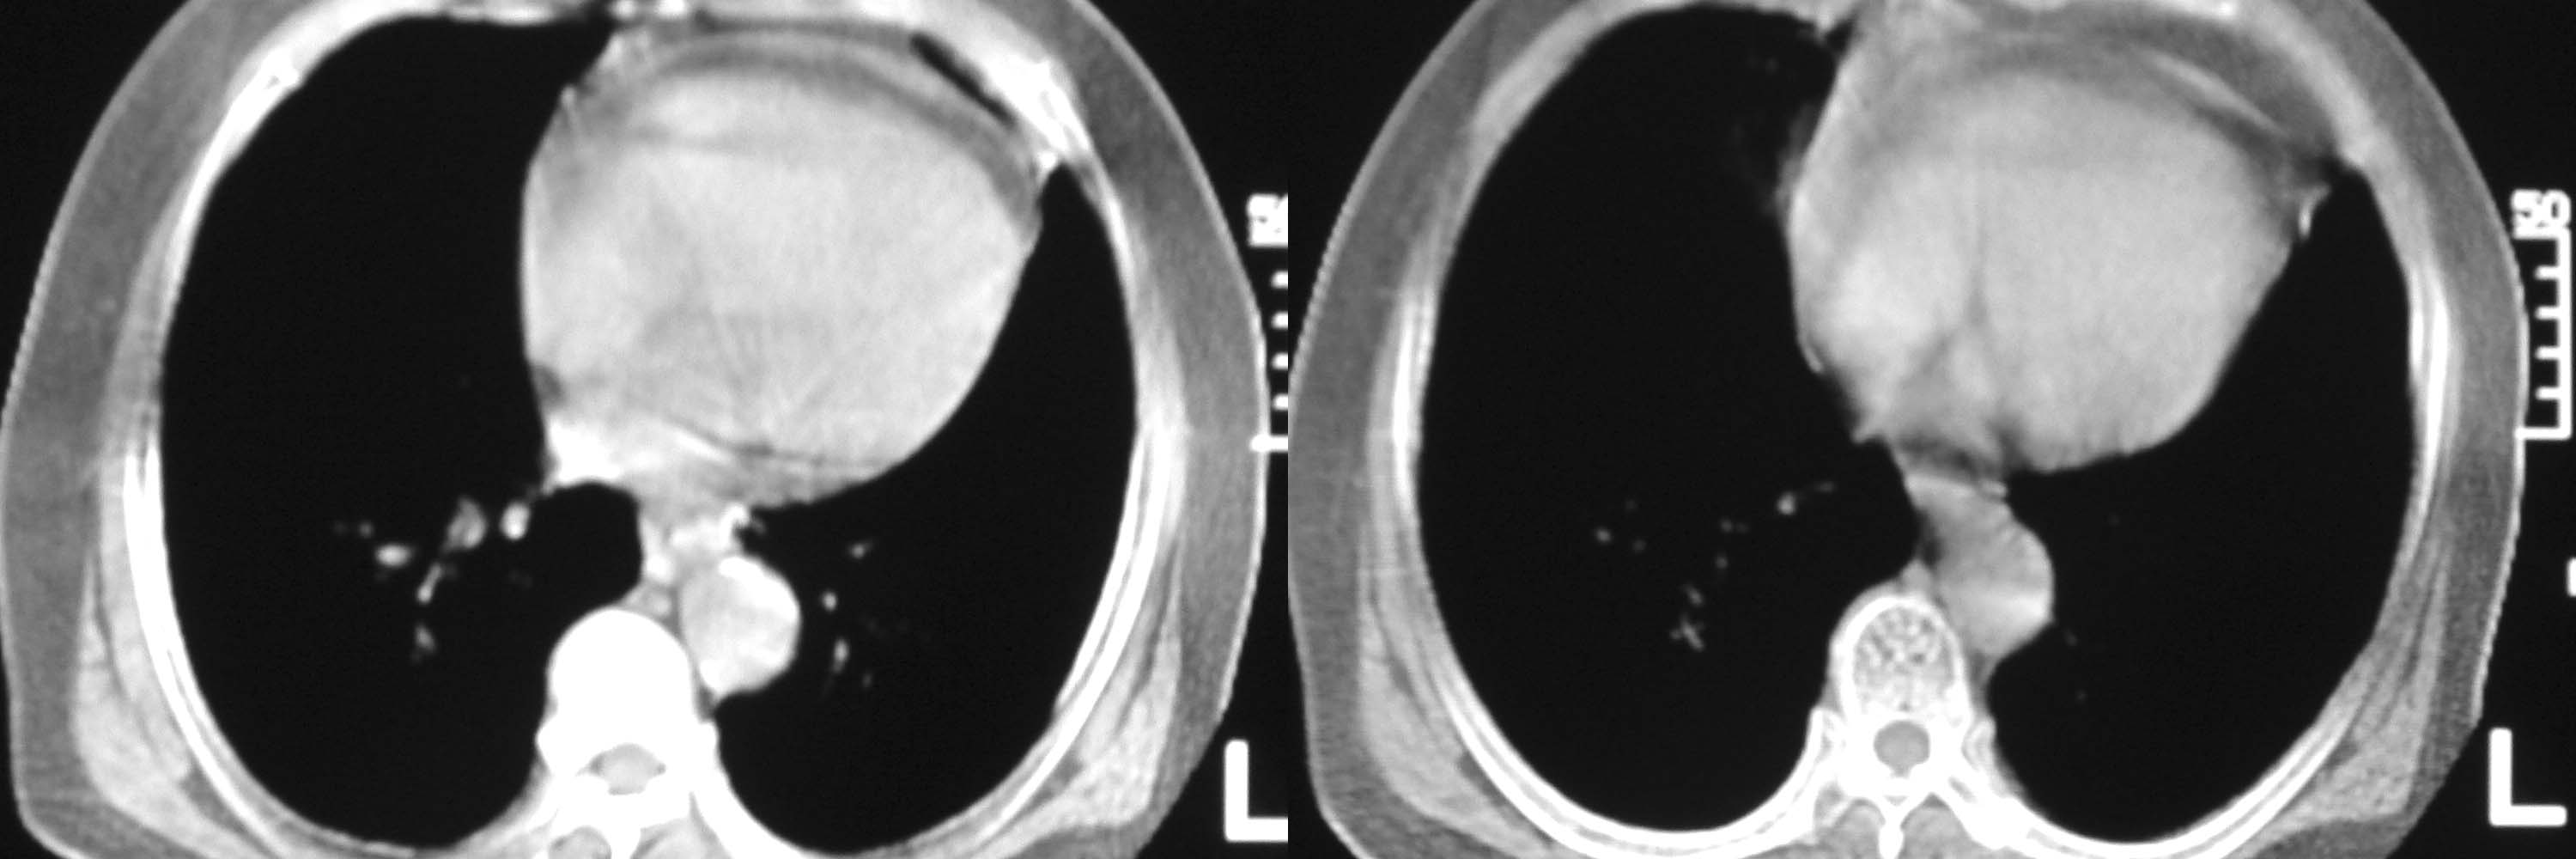

女78岁咳嗽咳痰无咳血平片报右上肺不张、慢支、肺气肿、请老师们帮忙看看,箭头所指是什么?是占位吗?有肺气肿吗?谢谢

箭头所指考虑血管影;纵隔内及双肺门区多发淋巴结钙化;不支持肺气肿。

箭头所指考虑血管影(头臂血管);纵隔内及双肺门区多发淋巴结钙化;不支持肺气肿。